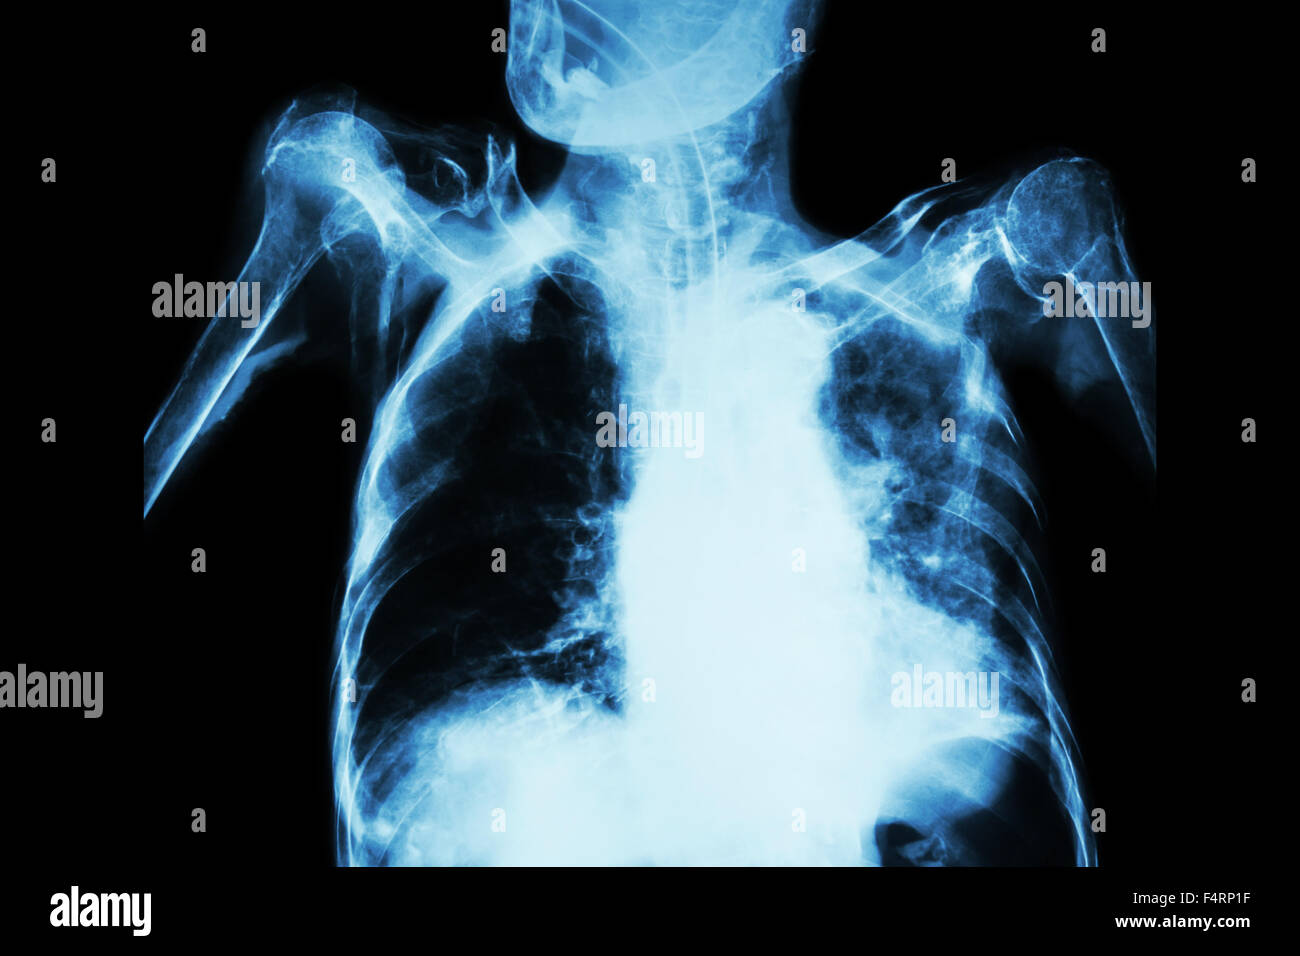

Chest X Ray Of Tb Patient . Abnormalities on chest radiographs may be suggestive of, but are never diagnostic of tb, but can be used to rule out pulmonary tb. because of these limitations, imaging plays an important role in evaluation of chest tb (ctb) patients and ct is more sensitive than cxr in this regard. [ 3, 4] for optimal management, the radiologists are often.

because of these limitations, imaging plays an important role in evaluation of chest tb (ctb) patients and ct is more sensitive than cxr in this regard. Abnormalities on chest radiographs may be suggestive of, but are never diagnostic of tb, but can be used to rule out pulmonary tb. [ 3, 4] for optimal management, the radiologists are often.

Chest X Ray Of Tb Patient Abnormalities on chest radiographs may be suggestive of, but are never diagnostic of tb, but can be used to rule out pulmonary tb. [ 3, 4] for optimal management, the radiologists are often. because of these limitations, imaging plays an important role in evaluation of chest tb (ctb) patients and ct is more sensitive than cxr in this regard. Abnormalities on chest radiographs may be suggestive of, but are never diagnostic of tb, but can be used to rule out pulmonary tb.